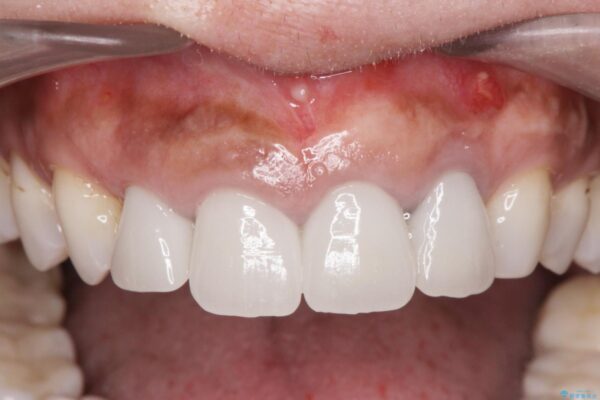

治療中

歯槽堤保存術を併用したブリッジ治療 治療中画像 歯槽堤保存術を併用したブリッジ治療 治療中画像 歯槽堤保存術を併用したブリッジ治療 治療中画像 歯槽堤保存術を併用したブリッジ治療 治療中画像 歯槽堤保存術を併用したブリッジ治療 治療中画像 歯槽堤保存術を併用したブリッジ治療 治療中画像 歯槽堤保存術を併用したブリッジ治療 治療中画像